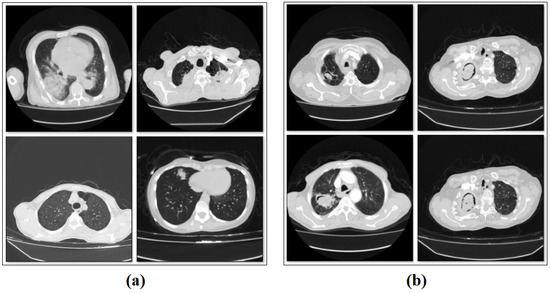

In this retrospective study, a total of 168 patients with pathologically diagnosed aspergilloma and diseases confused with aspergilloma between 2011 and 2024 were included. The images of the dataset were obtained from the department of Fırat University Research Hospital (Elazig, Turkey). Eighty-four of the patients were pathologically diagnosed with aspergilloma, and the other 84 patients had diseases confused with aspergilloma. In the chest CT scans of the patients in both groups, two chest CT images of the disease were obtained, and a total of 336 slices were obtained. There were 48 male and 36 female patients in the aspergilloma group and 52 male and 32 female patients in the non-aspergilloma group. The mean age of the aspergilloma group was 64.6 ± 13.8 years and the mean age of the non-aspergilloma group was 60.3 ± 16.8 years. The other class of the dataset included 168 CT images without aspergilloma disease. Thus, the dataset consists of 168 images with aspergilloma and 168 images without aspergilloma. The classes are balanced in number. The total number of original images is 336. An example subset of images related to the types of the dataset is shown in Figure 1.

Figure 1. Sample images from the classes/types of the dataset: (a) patients without aspergilloma, and (b) patients with aspergilloma.